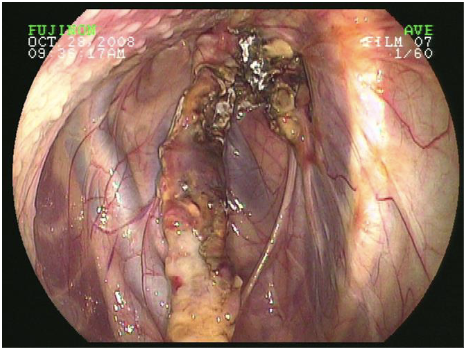

larynx endoscopic view

arytenoids, aryepiglottic fold, vocal folds, laryngeal saccule, epiglottis

laryngeal hemiplagia

half paralysis

aBduct- to move away from midline done by dorsal cricoarytenoid muscle (innervated by left recurrent laryneal nerve)

aDduct- move towards middline